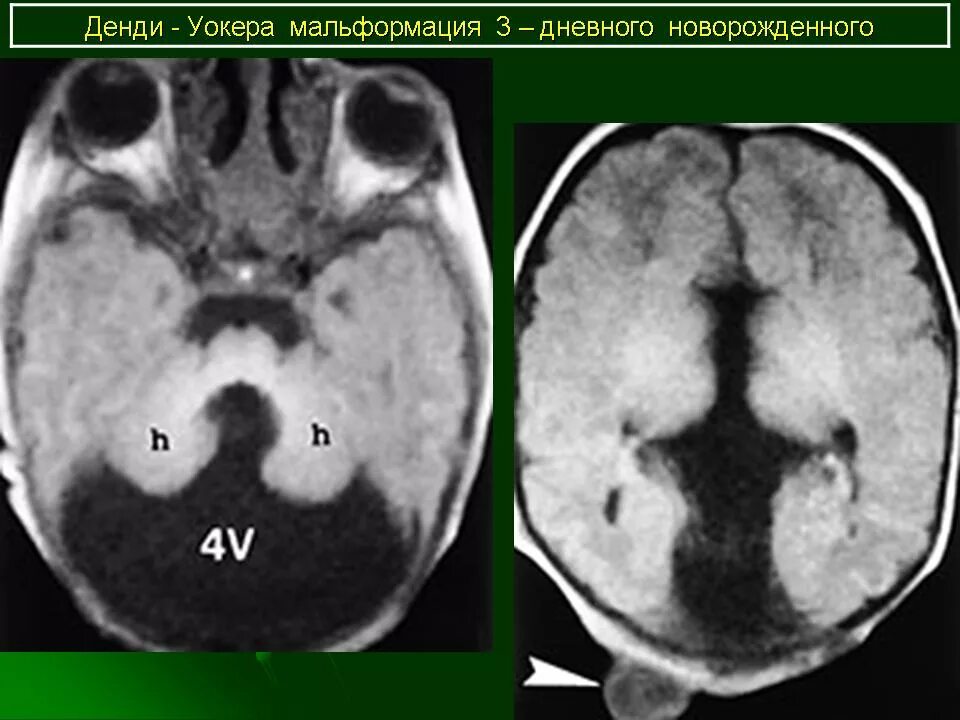

Денди уокера мрт